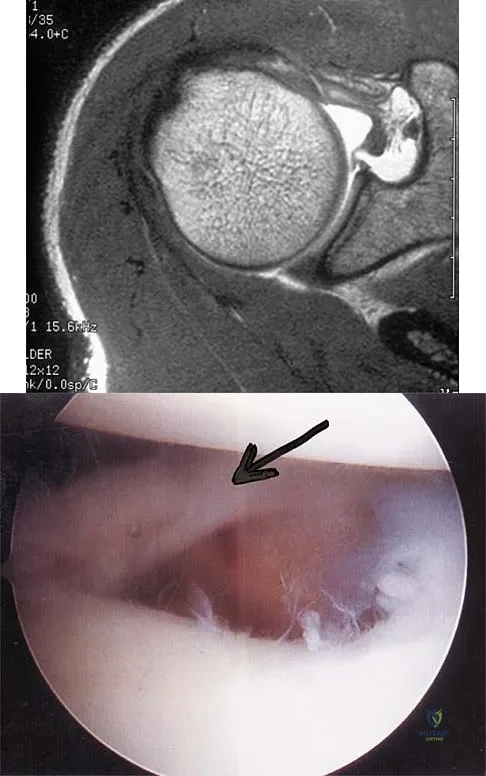

Question 45:

A patient has right shoulder pain. Figure 1a shows a gadolinium-enhanced transverse MRI scan at the level of the coracoid. Figure 1b shows an arthroscopic view of the anterior structures from a posterior portal. These images reveal which of the following findings?

Correct Answer: Normal anatomic variant (Buford complex)

Explanation:

The area shown in the arthroscopic view and MRI scan is referred to as a Buford complex and represents a normal labral variant. It consists of a thickened, cord-like middle glenohumeral ligament, a superior labral attachment of the middle glenohumeral ligament just anterior to the biceps tendon, and absence of the anterosuperior labrum. This combination of findings can be confusing and may simulate labral pathology. Mistaken repair of the lesion back to the glenoid rim can result in significant loss of external rotation. A Bankart lesion would be located at the inferior anterior glenoid rim. The subscapularis is seen anterior to the labrum. Normal variations that occur in the anterosuperior labrum can simulate pathology. Gusmer PB, Potter HG, Schatz JA, et al: Labral injuries: Accuracy of detection with unenhanced MR imaging of the shoulder. Radiology 1996;200:519-524. Griffin LY (ed): Orthopaedic Knowledge Update: Sports Medicine. Rosemont, IL, American Academy of Orthopaedic Surgeons, 1994, pp 47-63.